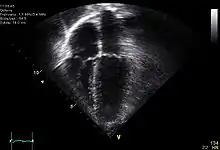

Ecocardiografía

Se utiliza para crear imágenes del corazón que son más detalladas que las imágenes obtenidas por una radiografía simple. Se pueden obtener imágenes en tiempo real en dos o tres dimensiones. Permite evaluar el funcionamiento de las válvulas cardíacas, para el diagnóstico de estenosis o insuficiencia, y para evaluar la contracción del músculo cardíaco, para el diagnóstico de hipertrofia o dilatación de los ventrículos y aurículas.

Se puede hacer una ecocardiografía de esfuerzo para comprobar el funcionamiento del miocardio para bombear la sangre al cuerpo. Se utiliza para detectar una disminución en el flujo sanguíneo al corazón, producido por un estrechamiento de las arterias coronarias.[17]

- Modo M (movimiento): Esta configuración es utilizada para analizar el movimiento de las estructuras del cuerpo de forma cualitativa y cuantitativa, como en el caso de las valvulas del corazón. Es un modo híbrido entre A y B, ya que el brillo de cada línea es modulado a la amplitud de los ecos como en el modo B, pero los ecos son recogidos en una sola dirección, a lo largo del recorrido del rayo como en el modo A.[22]